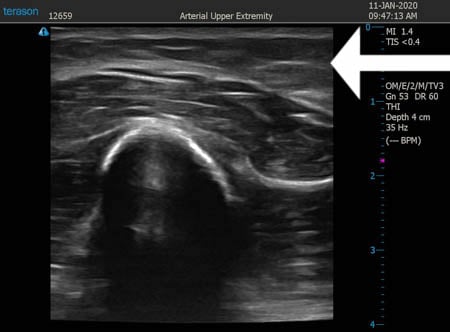

いつものように3Dタッチビュー(超音波)で

皮下脂肪層を評価してみましょう。

右二の腕

↓ ↓ ↓

上の画像の部分の皮下脂肪層をつまんでみましょう。